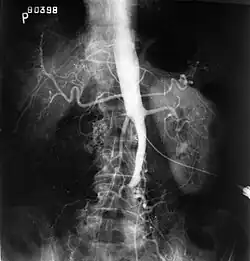

Plate from Gray's Anatomy showing the abdominal aorta and the common iliac arteries | |

Angiography provides important information regarding the perfusion and patency of distal arteries (e.g. femoral artery). The presence of collateral arteries in the pelvic and groin area is important in maintaining crucial blood flow and lower limb viability. However, angiography should only be used if symptoms warrant surgical intervention.[2]